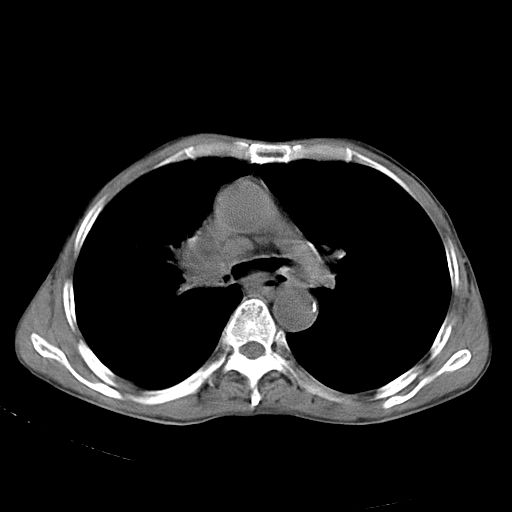

以下是引用苯小孩在2007-5-24 12:47:00的发言:[br]右侧肺门处不均匀密度软组织块影,远端肺组织见斑片模糊影,纵隔内淋巴结明显肿大,边界不清.<纵隔窗第12层面支气管内似见软组织结节>[br]考虑:1、右侧中央性肺癌并阻塞性肺炎并纵隔淋巴结转移可能性大.建议强化或纤支镜进一步检查.[br]2、隆突下淋巴结肿大/食道病变?请做鉴别检查.

以下是引用zhangzhongshou在2007-5-24 12:55:00的发言:[br]1、右肺中叶中心型肺癌并右肺门、隆突下、纵隔淋巴结转移。右肺中叶阻塞性肺炎。

以下是引用jw-830在2007-5-24 15:24:00的发言:[br][br] [br] 考虑右肺中央型肺癌并阻塞性炎症,右肺门及纵隔淋巴结转移。 [br] [br][br]